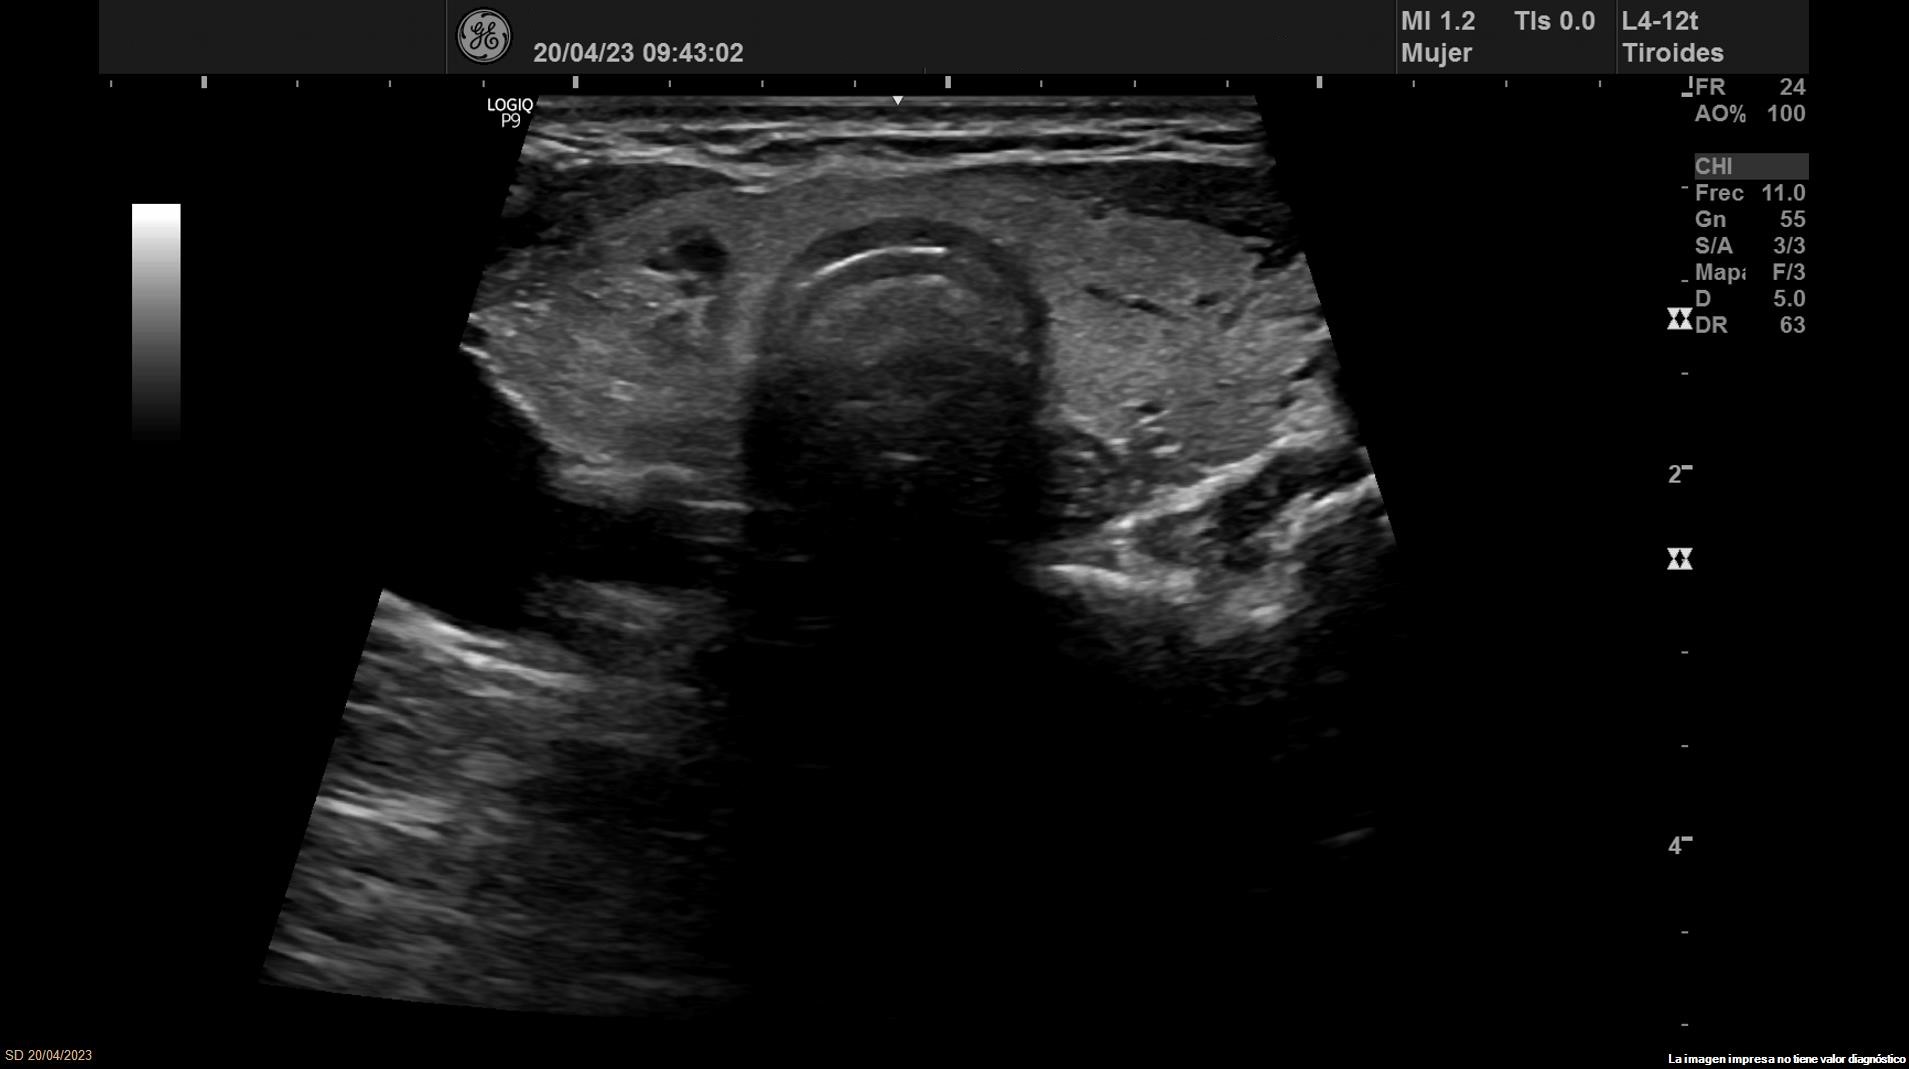

• Lóbulo tiroideo derecho: tamaño normal. En tercio inferior nódulo único espongiforme con área quística inferior que mide 15 mm de diámetro mayor longitudinal (ATA: baja sospecha).